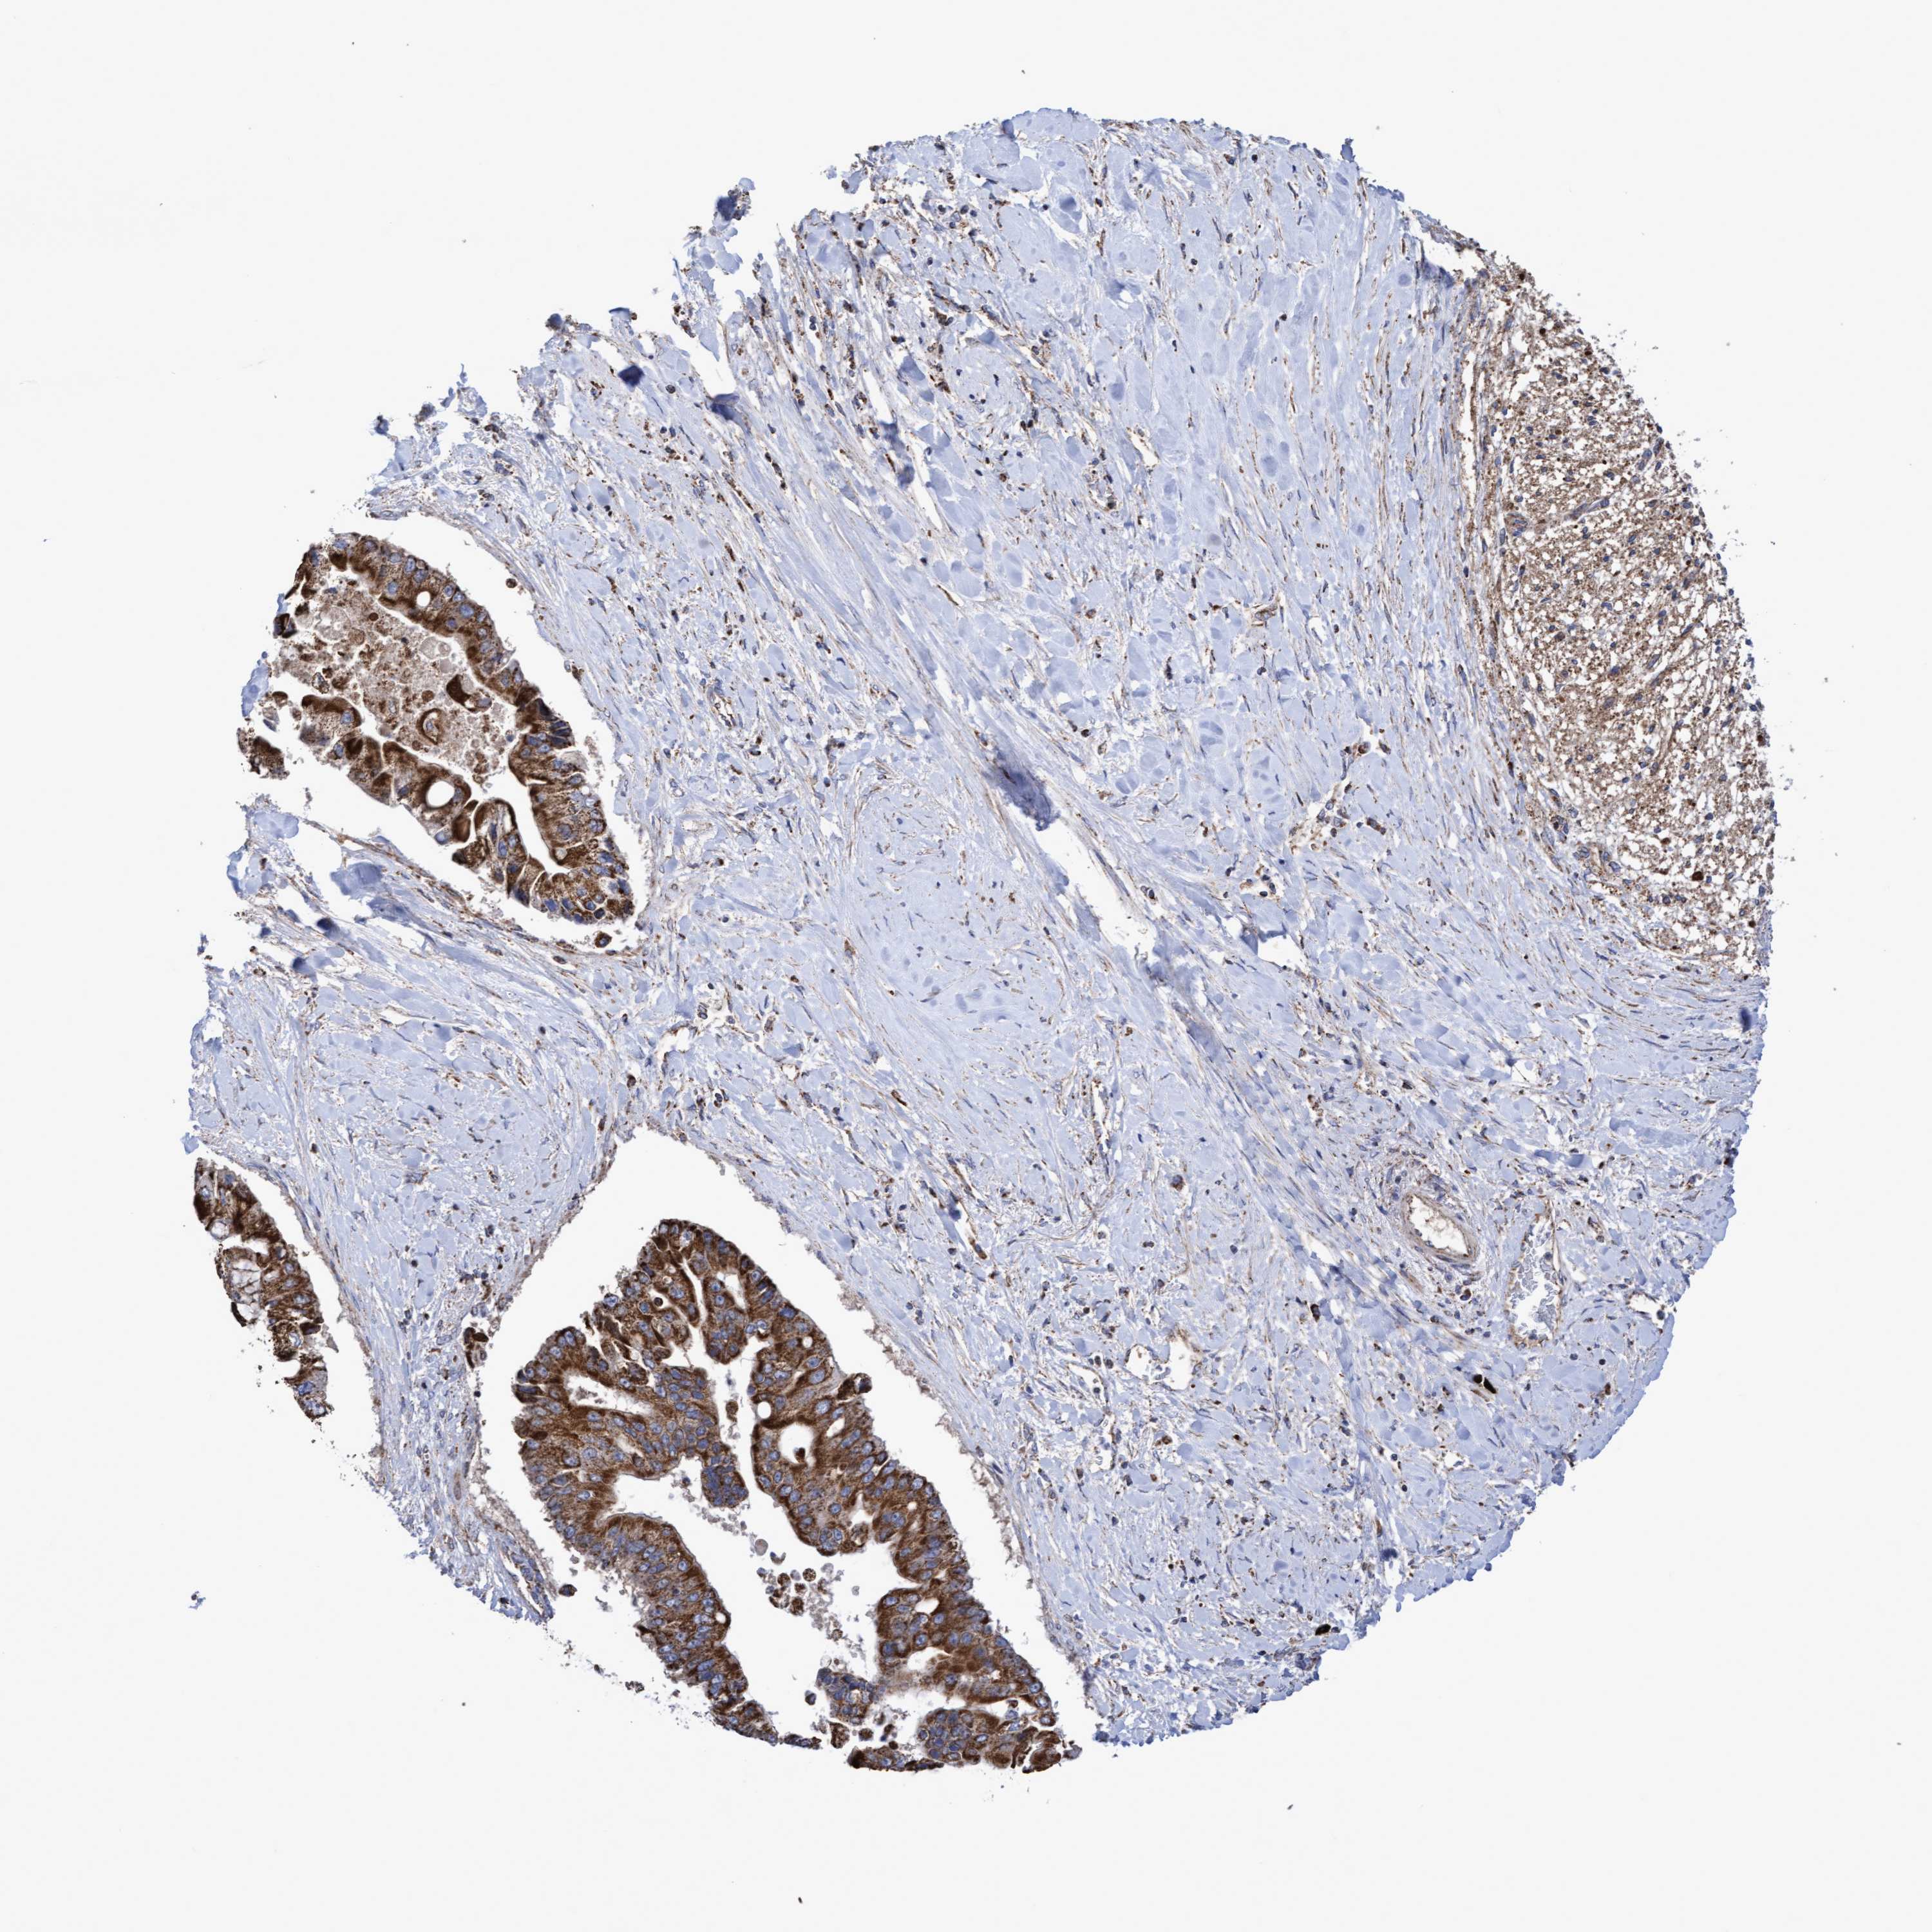

LIVER CANCER - Protein expressioni

A mouse-over function shows sample information and annotation data. Click on an image to view it in a full screen mode. Samples can be filtered based on level of antibody staining by selecting one or several of the following categories: high, medium, low and not detected. The assay and annotation is described here.

Note that samples used for immunohistochemistry by the Human Protein Atlas do not correspond to samples in the TCGA dataset.

Antibody stainingi

Antibody staining in the annotated cell types in the current human tissue is reported as not detected, low, medium, or high, based on conventional immunohistochemistry profiling in selected tissues. This score is based on the combination of the staining intensity and fraction of stained cells.

Each image is clickable and will lead to virtual microscopy that enables deeper exploration of all samples and also displays staining intensity scores, fraction scores and subcellular localization as well as patient and tissue information for each sample.

Antibody HPA019033

Antibody HPA019167

Staining

High

Medium

Low

Not detected

Intensity

Strong

Moderate

Weak

Negative

Quantity

>75%

75%-25%

<25%

None

Location

Nuclear

Cytoplasmic/membranous

Cytoplasmic/membranous,nuclear

Cholangiocarcinoma

Carcinoma, Hepatocellular, NOS